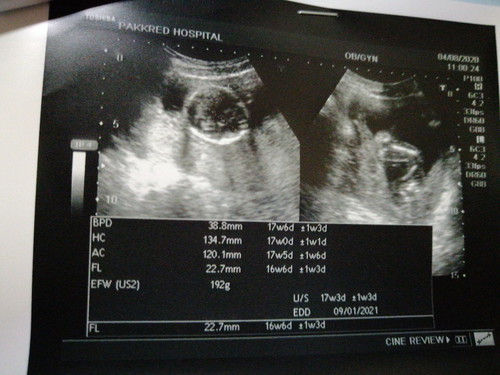

แม่ๆคะช่วยอ่านใบอัลตร้าซาวด์ให้หน่อยได้ไหมคะ น้ำหนักน้องใช่192กรัมรึเปล่าคะ ในรูปดูไม่รู้ว่าเป็นเด็กเลยค่ะ ถือว่าปกติไหมคะแม่ๆ หมอไม่ได้แจ้งอะไรมาเลยค่ะ ปริ๊นท์รูปมาแล้วก็แปะลงในสมุดแค่นี้ค่ะ รบกวนหน่อยนะคะ🙏